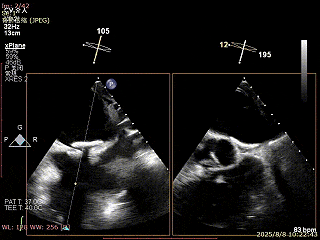

XPLAN切面2区偏3区中重度反流

3D enface 切面

3D enface观察反流